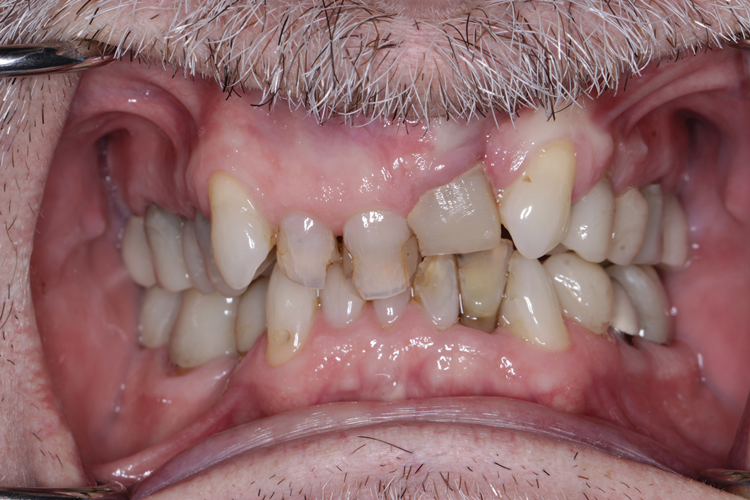

(7.) Pretreatment retracted view of a 60-year-old male patient who presented to receive comprehensive care and full-mouth rehabilitation to enhance his function, stability, and esthetics. Due to his malocclusion at the time of presentation, adult orthodontic treatment was recommended. Given the patient’s anterior deep vertical overlap, the decision was made to temporarily challenge his vertical dimension of occlusion to facilitate ease of bracketing the mandibular anterior teeth. This was to be achieved with posterior full-coverage composite crowns.

Figure 7